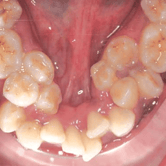

Dientes Supernumerarios

Los dientes supernumerarios son dientes adicionales que pueden aparecer en la boca y causar problemas de alineación o erupción de otros dientes.

Los pacientes pueden notar dientes adicionales en la boca, lo que puede causar apiñamiento o problemas estéticos.

El tratamiento incluye la extracción quirúrgica de los dientes supernumerarios.

Dientes impactados

Los dientes impactados son dientes que no pueden erupcionar correctamente debido a la falta de espacio o a una obstrucción.

Los pacientes pueden notar que un diente no ha salido, aunque debería haberlo hecho. Esta condición es común con las muelas del juicio y los caninos superiores.

El tratamiento puede incluir la extracción del diente impactado o la creación de espacio para permitir su erupción.